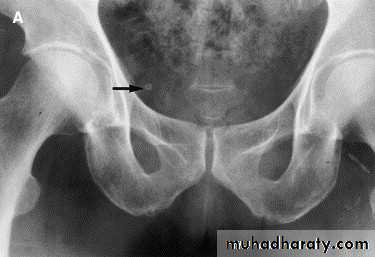

*Phlebolith (arrow):-round lucent centre,,it represents calcified thrombus in pelvic vein.